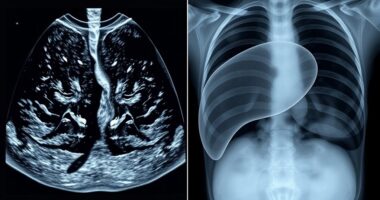

Organ-Ultraschall und Röntgen: Wie die Lunge und die Leber auf Metastasen untersucht werden

Die Techniken zur Beurteilung von Lungen- und Lebermetastasen—Ultraschall und Röntgen—bieten Einblicke, die Sie überraschen könnten, wenn Sie ihre Stärken und Schwächen entdecken.